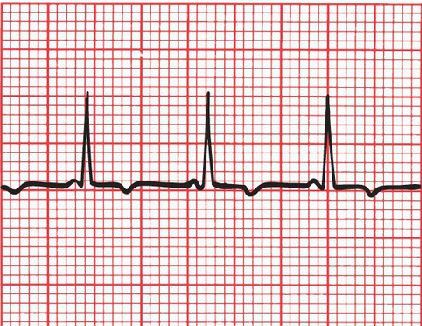

Identify this ECG

In LGL syndrome, the PR interval is short, but there is no delta wave.

PR<0.12

Normal QRS

No delta waves